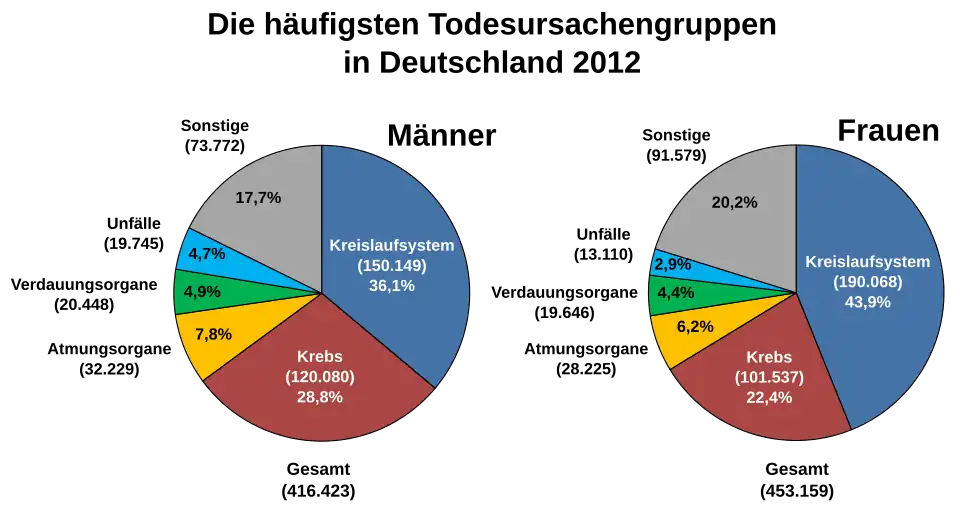

Krebs ist in Deutschland nach den Herz-Kreislauf-Erkrankungen die zweithäufigste Todesursache. Dennoch ist nicht jeder Krebsverlauf tödlich, falls rechtzeitig eine Therapie begonnen wird oder ein langsam wachsender Krebs erst in so hohem Lebensalter auftritt, dass der Patient an einer anderen Todesursache verstirbt. Die aktuellen von der Gesellschaft der epidemiologischen Krebsregister in Deutschland e. V. (GEKID) 2017 veröffentlichten relativen 5-Jahres-Überlebensraten über alle Krebsarten beziehen sich auf Patienten, die 2013 und 2014 erkrankten. Für Frauen lag der Wert bei 65 %, für Männer bei 59 %.[3] In nordeuropäischen Ländern gibt es noch günstigere Werte. In Finnland lagen beispielsweise die 5-Jahres-Überlebensraten von Frauen und Männern, die 2014–2016 erkrankten, bei 68,6 % bzw. 66,3 %.[4] Als geheilt wird in der Onkologie ein Patient bezeichnet, der mindestens fünf Jahre lang ohne Rückfall (Rezidiv) überlebt. Diese Definition von „geheilt“ ist problematisch, weil viele Rückfälle erst zu einem späteren Zeitpunkt erfolgen. Es fließen mithin Patienten in die Krebs-Erfolgsstatistik ein, die später an den Folgen von Krebs sterben. Allerdings nähert sich bei den meisten Krebsarten innerhalb rezidivfrei überlebten fünf Jahren die durchschnittliche Lebenserwartung derjenigen von Gleichaltrigen an.

Statistik

Qualitativ hochwertige Daten zur Krebsinzidenz weltweit werden seit den 1960er Jahren gesammelt und von der Internationalen Agentur für Krebsforschung (IARC), einer Organisation der Weltgesundheitsorganisation (WHO), veröffentlicht. Die WHO veröffentlicht für ausgewählte Länder zudem Daten zur Krebsmortalität. Etwa für ein Sechstel der Weltbevölkerung liegen Daten zur Inzidenz vor, für ein Drittel Daten zur Mortalität.[62] In Deutschland veröffentlicht das Robert Koch-Institut zusammen mit der Gesellschaft der epidemiologischen Krebsregister in Deutschland e. V. (GEKID) alle zwei Jahre den Bericht Krebs in Deutschland. 2015 erschien die 10. Ausgabe mit Daten bis zum Jahr 2012.[63] In der Schweiz erscheint alle fünf Jahre ein Bericht, 2016 die zweite Ausgabe.[64]

Die Zahl der diagnostizierten Krebserkrankungen steigt weltweit an. Die WHO gibt für 2012 an, dass 14,1 Millionen Menschen an Krebs erkrankt sind – 11 Prozent mehr als im Jahr 2008.[65] Die Anzahl der Krebstoten stieg im gleichen Zeitraum um 8 Prozent auf 8,2 Millionen. In der Schweiz wie in den westlichen entwickelten Ländern beruht der Anstieg auf der demografischen Alterung der Bevölkerung.[66]

Gleichzeitig fallen Inzidenz und Mortalität der meisten Krebsarten (inklusive Lunge, Darm, Brust und Prostata) in den Vereinigten Staaten (USA) und den meisten westlichen Ländern. „Wir beobachten seit 15 Jahren, dass die Krebssterblichkeit in den USA und Deutschland sinkt“, sagt Nikolaus Becker vom Deutschen Krebsforschungszentrum in Heidelberg. Den größten Anteil am Erfolg schreibt die US-Statistik der Darmkrebsfrüherkennung zu. Bei Männern sinkt die Lungenkrebs-Rate, weil sie weniger rauchen.[67]

In einigen Entwicklungs- und Schwellenländern steigen die Erkrankungsraten jedoch aufgrund der Übernahme eines ungesunden Lebenswandels (Rauchen, mangelnde körperliche Aktivität, Konsum energiedichter Nahrungsmittel). In ein paar dieser Länder liegen beispielsweise die Lungen- und Darmkrebsraten bereits über denen der Vereinigten Staaten. Entwicklungsländer sind jedoch immer noch überproportional von infektiösen Krebsarten betroffen (Gebärmutterhals, Leber, Magen).[62]

Die weltweit häufigsten Krebsarten sind Lungenkrebs, Brustkrebs und Darmkrebs.

Auf der x-Achse die altersstandardisierte Mortalitätsrate (erster Zahlenwert) und der prozentuale Anteil an den Krebserkrankungen (zweiter Zahlenwert in der Klammer).

Statistisch gesehen entwickelt jeder dritte Europäer im Laufe seines Lebens Krebs.[68] In Deutschland erkranken etwa 395.000 Menschen jährlich an Krebs, davon rund 195.000 Frauen und 200.000 Männer. Die meisten Fälle treten im Alter von über 60 Jahren auf. Die unter 60-Jährigen machen mit etwa 107.000 Fällen nur rund ein Viertel der Krebs-Neuerkrankungen aus. Einer US-Studie zufolge sterben weltweit jeden Tag etwa 20.000 Menschen an den Folgen einer Krebserkrankung. 2007 gab es demnach etwa 7,6 Millionen Tote durch Krebs – davon 4,7 Millionen in Entwicklungsländern. Die Gesamtzahl aller jährlich weltweit neudiagnostizierten Krebserkrankungen wird dieser Quelle nach mit 12,3 Millionen angegeben. Dies war die erste Schätzung dieser Art. Beim Tod durch die Folgen des Rauchens rechnen Forscher weiter mit steigenden Zahlen. Im 20. Jahrhundert sei der Tabakkonsum (vgl. Tabakrauch) Ursache für etwa 100 Millionen Todesfälle gewesen, im 21. Jahrhundert sei mit etwa einer Milliarde Toten zu rechnen.[69][70]

Aktuelle Situation in Deutschland

Krebs ist mit 500.000 Neuerkrankungen im Jahr ein zentrales Gesundheitsproblem in der Bundesrepublik, wie aus Statistiken 2018/2019 hervorging. Etwa die Hälfte der deutschen Bevölkerung erkrankt nach Angaben der Stiftung Deutsche Krebshilfe im Rahmen ihres Lebens an einer von über 200 Tumor-Arten.[86] Die häufigsten Neuerkrankungen sind Brustkrebs bei Frauen mit 71.900 Fällen und Prostatakrebs bei Männern mit 60.700 Neuerkrankungen im Jahr. Rund 2.000 Kinder und Jugendliche erkranken in der Bundesrepublik jedes Jahr neu an Krebs.[87]

2022 starben rund 231.500 Menschen in Deutschland an den Folgen von Krebs. Er war damit, nach Krankheiten des Kreislaufsystems, die zweithäufigste Todesursache. Im gleichen Jahr wurden rund 1,40 Millionen Patienten wegen einer Krebserkrankung im Krankenhaus behandelt. Mit einem Anteil von 8 % an allen Krankenhausaufenthalten war Krebs der vierthäufigste Behandlungsgrund.[88] In Deutschland können heutzutage (2024) etwa zwei Drittel der Krebspatienten geheilt werden, während in den frühen 1980er Jahren weniger als ein Drittel der Patienten die Erkrankung überlebte.[3][4] Die steigenden Heilungsraten sind vor allem auf Fortschritte in der modernen Medizin, wie zielgerichtete Therapien und Immuntherapien, zurückzuführen. Zusätzlich hat sich die Krebsbehandlung hin zu einem interdisziplinären Ansatz entwickelt, der zertifizierte Zentren und teambasierte Behandlungskonzepte nach aktuellen Leitlinien umfasst.[5]